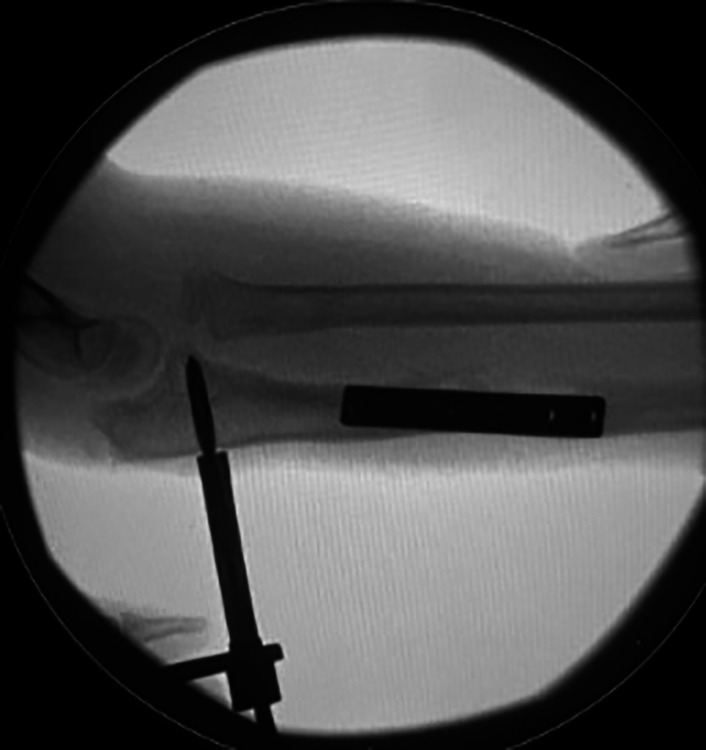

Introduction: Acquired chronic radial head (RH) dislocations present a significant surgical challenge. Coexisting deformity, length discrepancy, and RH dysplasia, in multiply-operated patients often preclude acute correction. This study reports the clinical and radiological outcomes in children, treated with hexapod frames for gradual RH reduction.

Materials and methods: Patient cohort from a prospective database was reviewed to identity all hexapod frames for RH dislocations between 2000 and 2021. Patient demographics, clinical range, and radiographic parameters were recorded.

Results: From a cohort of 127 upper limb frames, 34 chronic RH dislocations (15 anterior and 17 posterior) were identified. Mean age at surgery was 10 years (5-17 years). Six pathologies were reported (17 post-traumatic, 11 multiple hereditary exostosis (MHE), two nail-patella syndrome, two Ollier's disease, one osteogenesis imperfecta, and one rickets). About 76% had a congruent RH reduction at final follow-up. Two MHE cases gradually re-dislocated. Five children had some mild persistent incongruency. Mean follow-up duration was 4.2 years (9 months to 11.5 years). Mean radiographic correction achieved in coronal plane 9°, sagittal plane 7°, and carrying angle 12°. Mean ulnar length gained was 7 mm, and final ulnar variance was 7 mm negative (congenital). All cases achieved bony union, with two requiring secondary bone grafting. Mean frame duration was 166 days. Mean final range of motion was 64° supination, 54° pronation, and 2°-138° flexion.

Conclusion: The majority of children having frame correction achieve complete correction or minor subluxation, which is well tolerated clinically. Frame-assisted reduction is an effective tool for selective complex cases, irrespective of the pathology driving the RH dislocation.